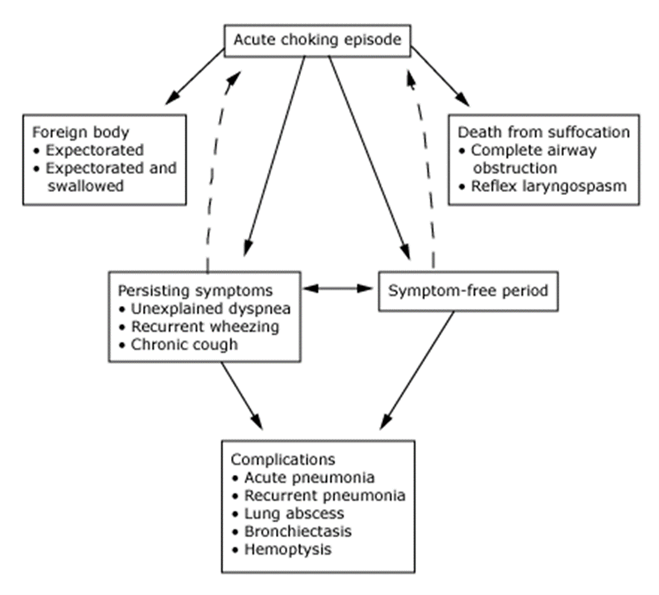

Natural Course of FB Aspiration: The natural course of FB aspiration can vary. Some FBs may remain lodged in the airway, causing obstruction and inflammation, while others may migrate to different locations.

Chart 1: Natural Course of FB Aspiration [1].